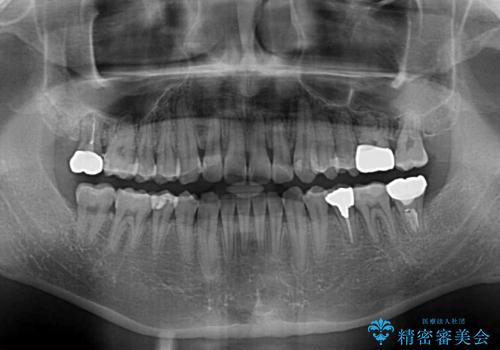

- 虫歯が多く、セラミッククラウンにより虫歯治療を行っている途中で矯正治療をしたいとのことで来院された患者様です。

上顎前歯が舌側に転位しており、なるべく早く楽に矯正したいとのことで、ワイヤー矯正を行うこととしました。

虫歯治療途中の歯は仮歯が装着されていたため、そのまま矯正治療を行い、矯正後に補綴治療を行うこととしました。

インビザライン矯正では苦手とする舌側転位した前歯をスムーズに改善することができました。

矯正治療により歯磨きがしやすくなったので、虫歯予防のセルフケアが行いやすい環境となりました。